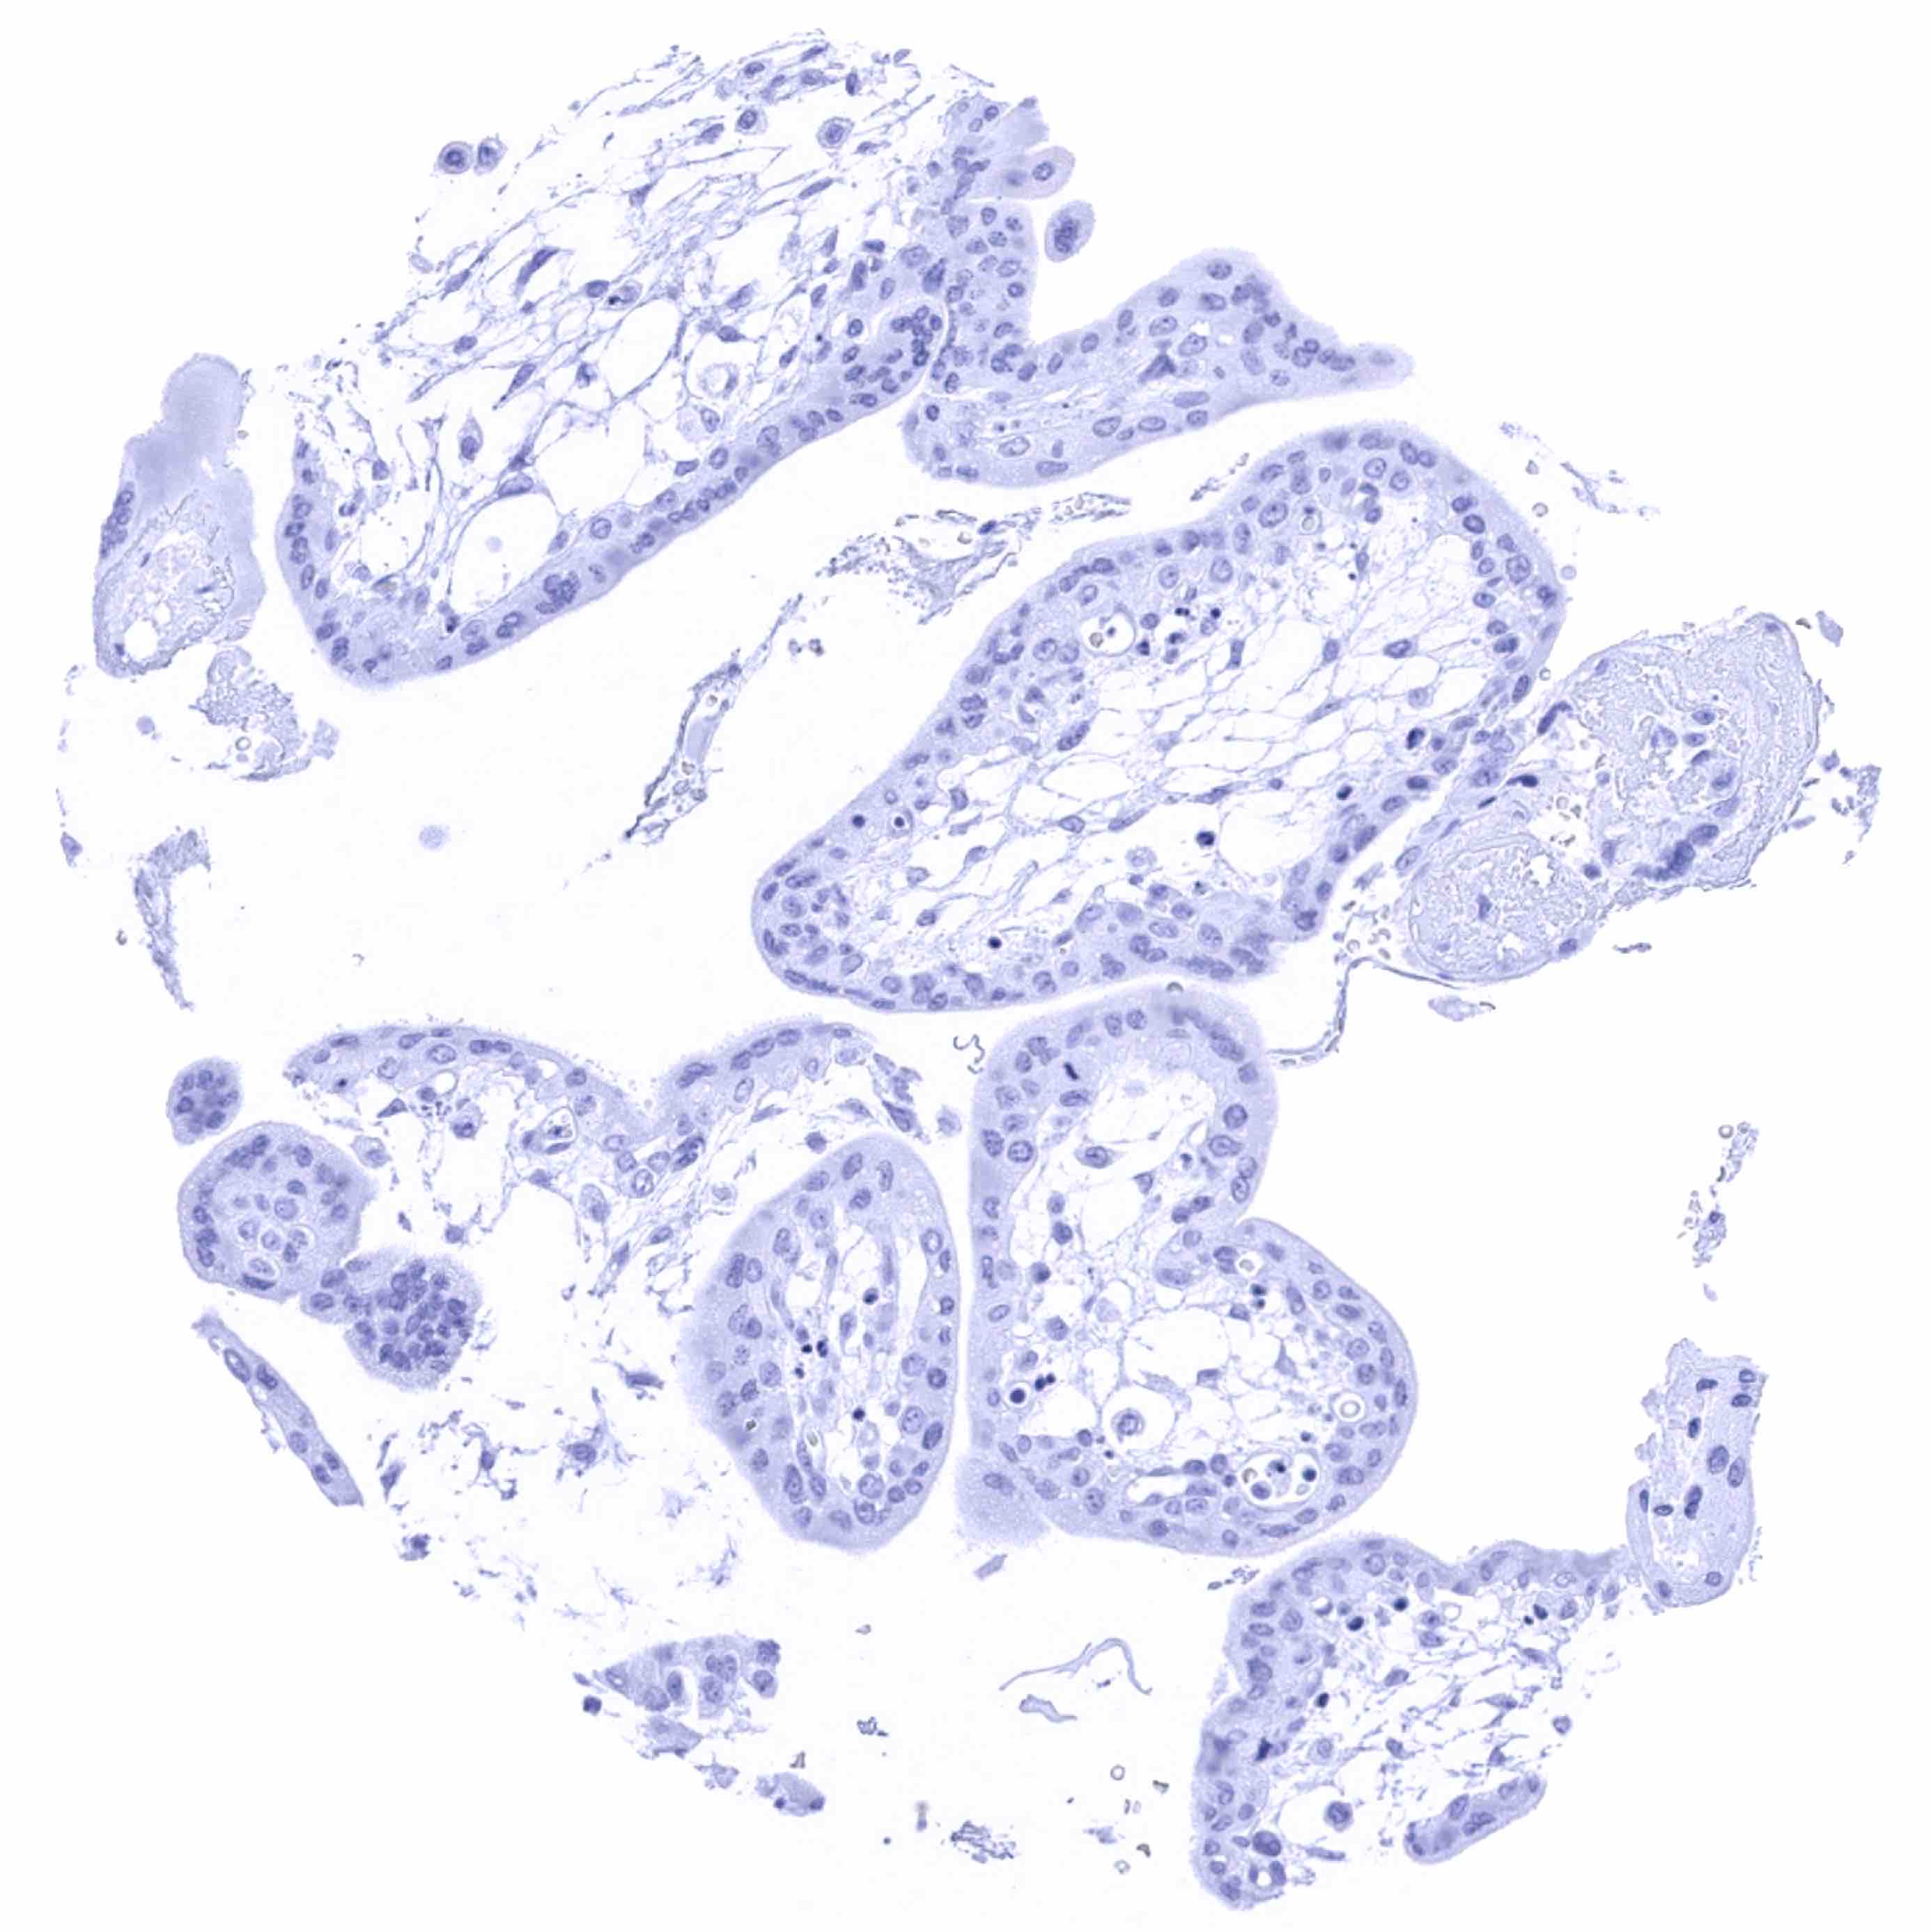

Testis